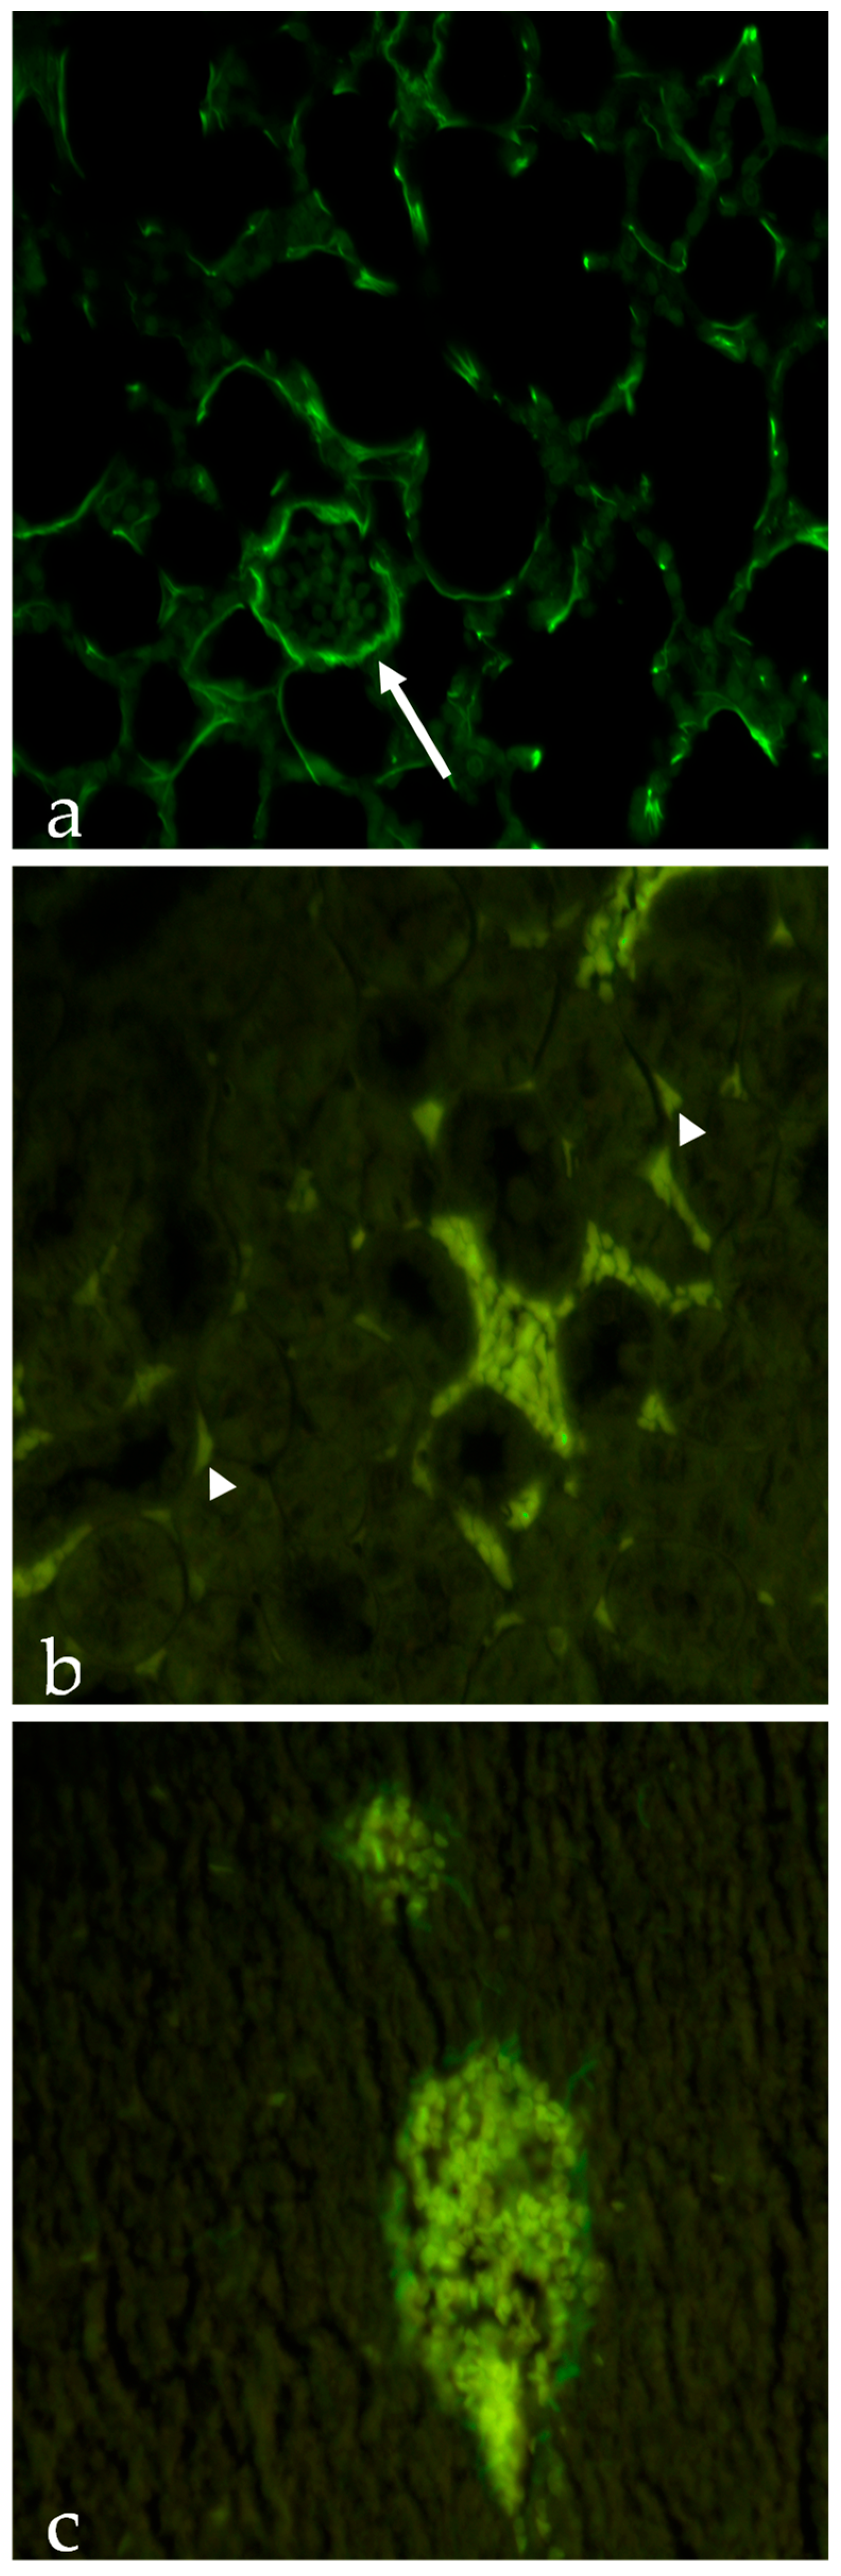

As it can be seen from Table 6, NP accumulation in serum is very similar for both P and PP NPs. Contrariwise, only PP NPs are detectable in the analysed organs. These data were also corroborated by results of histological experiments shown in Figure 4. These outcomes indicated that PP NPs could be detected in the lungs (Figure 4a) and, to a lesser extent, within the kidneys (Figure 4b), indicating the prompt elimination of P NPs from these organs. As for PP NPs, the slight uptake in the lungs is clearly detectable in the intercellular spaces around pneumocytes composing alveolar structures and around blood vessels, whereas in the kidneys, PP NPs are located inside blood vessels and in the intercellular spaces around tubules. Figure 4c shows that in the liver, PP NPs could be detected only inside blood vessels.

Figure 4. Photomicrograph of poly(lactic-co-glycolic) acid (PLGA)-Poloxamer nanoparticles (PP NPs): (a) in the lungs, PP NPs are clearly detectable in the intercellular spaces around pneumocytes composing alveolar structures and around blood vessels (arrow); (b) in the kidneys, PP NPs are located inside blood vessels and in the intercellular spaces around tubules (arrowheads); (c) in the liver, PP NPs can be detected only inside blood vessels. Original magnification was 40× in all micrographs.